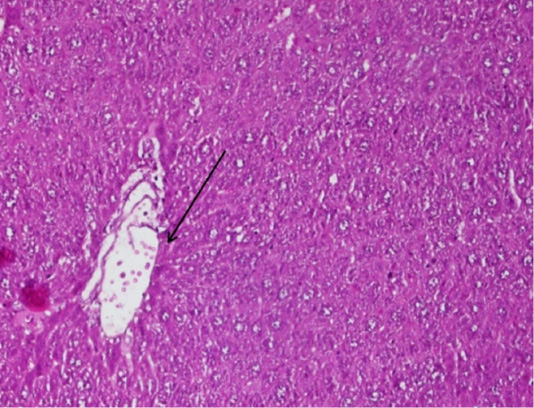

Figure 2

The arrow shows the figure of fibrosis tissue in the blood smear P of the mice (Mus Musculus) hepatic, the supply used Hematoxylin Eosin (HE) 200x magnification.